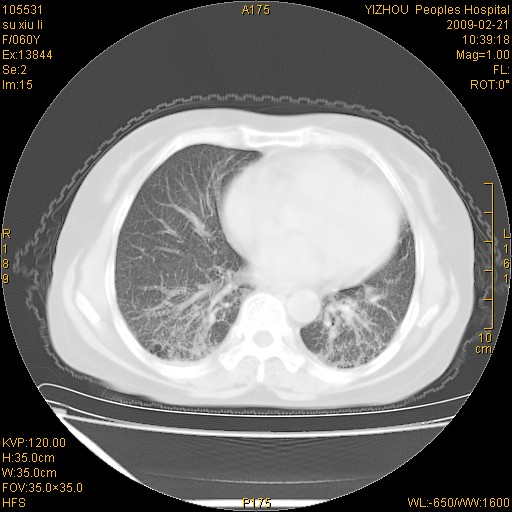

标题: CT18259:两肺间质纤维化?

女,60岁,反复咳嗽1月。

两肺支扩,以肺为著合并双肺较广范纤维化病变。建议除外结核等病变。

两下肺支扩

符合间质感染,部分纤维化表现

特发性间质纤维化

特发性间质纤维化伴支扩!